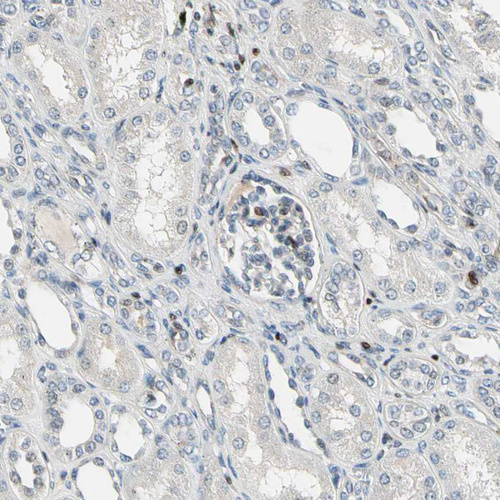

Immunohistochemical staining of human skin shows moderate to strong nuclear positivity in keratinocytes.